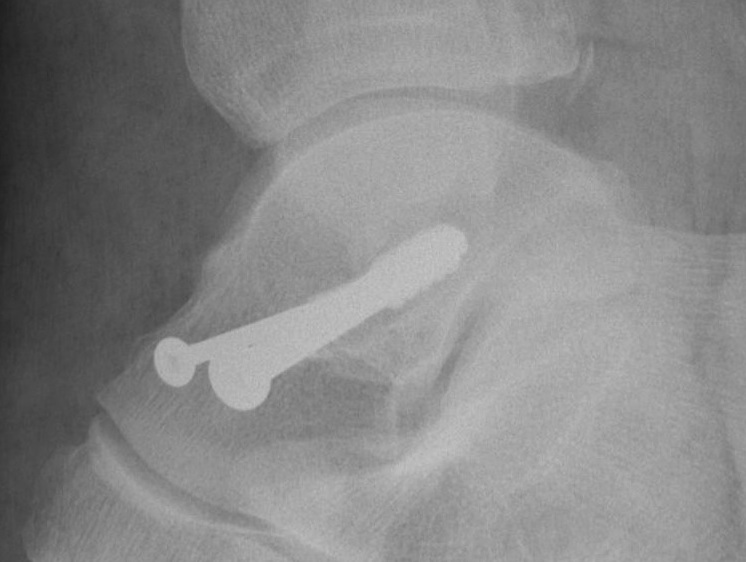

Cannulated screws

Xrays

| AP | Lateral | Canale View |

|---|---|---|

| Entry point of the screws |

Evaluate neck reduction

|

Evaluates the neck reduction |

Lateral off articular surface Medial through articular cartilage |

Depth of screws |

Beam angled 75o to foot Foot 15o pronated |

2. Antegrade (posterior to anterior) screws

- between FHL and peroneals

- entry point lateral tubercle talus

- bury to avoid posterior impingement

Antegrade screws